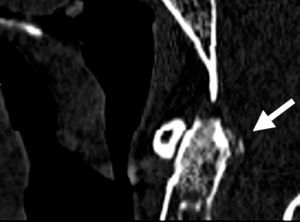

La afectación del esqueleto axial por condrocalcinosis ha estado asociada a depósitos cálcicos en disco intervertebral, ligamento amarillo, articulaciones facetarias e incluso articulaciones sacroilíacas. La calcificación del ligamento transverso del atlas (figs. 1-3) es una manifestación menos frecuente y se ha denominado síndrome de Crown Dens; constituye un cuadro clínico asintomático en la mayoría de las ocasiones, pero también puede estar asociado con brotes agudos de dolor cervical, rigidez y fiebre con las connotaciones de dificultad diagnóstica añadidas en estos casos.

En los estudios radiológicos realizados destaca la aparición de una espondiloartrosis cervical y calcificaciones en el ligamento transverso del atlas y ligamentos alares a nivel de la articulación atlo-axoidea (fig. 4).

El síndrome de Crowned Dens fue descrito por primera vez en 1985 por Bouvet et al1,2. El diagnóstico se basa en la asociación de un cuadro clínico compatible y unos hallazgos en las pruebas de imagen, fundamentalmente depósitos cálcicos en ligamentos de la articulación atlo-axoidea, visibles en la TC3,4.